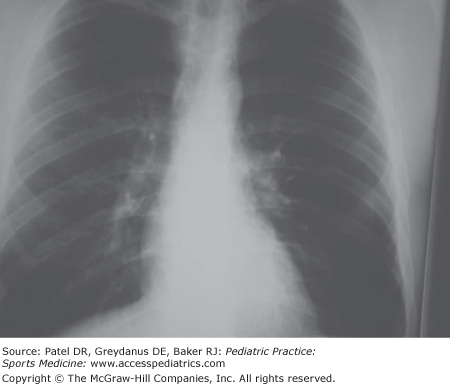

The athlete experiences chest pain on deep inspiration, shortness of breath, and tachycardia. Breath sounds are diminished over the affected area. The pneumothorax may be stable or may be expanding or “tension” pneumothorax (Figure 37-2). The tension pneumothorax is a medical emergency and should be identified clinically when there is rapidly deteriorating shortness of breath (Figure 37-3). Trachea may be deviated to the uninvolved side. A rattling sound or sensation in the anterior chest is known as Hagemen’s sign and indicates pneumomediastinum.

If clinical signs suggest tension pneumothorax in an unstable patient, treatment should be started rather than delayed while awaiting an x-ray. For the stable patient with pneumothorax, the x-ray should be obtained to confirm the diagnosis and treatment based on percent of lung collapse.

The tension pneumothorax can be aspirated immediately with 14 gauge needle inserted in the second intercostal space. Placement of a chest tube or catheter will allow the lung to re-expand. Percentage of lung collapse is estimated on the chest film. Stable pneumothorax less than 20% can be observed and managed conservatively. Pneumothorax greater than 20% should be re-expanded with placement of chest tube. Oxygen administration is indicated and will help with dyspnea. In cases of recurrent pneumothorax, surgical pleurodesis will be required. Return to sports should not be attempted prior to 2 weeks following complete resolution with gradual return to unrestricted sports participation over the subsequent 8 to 12 weeks.